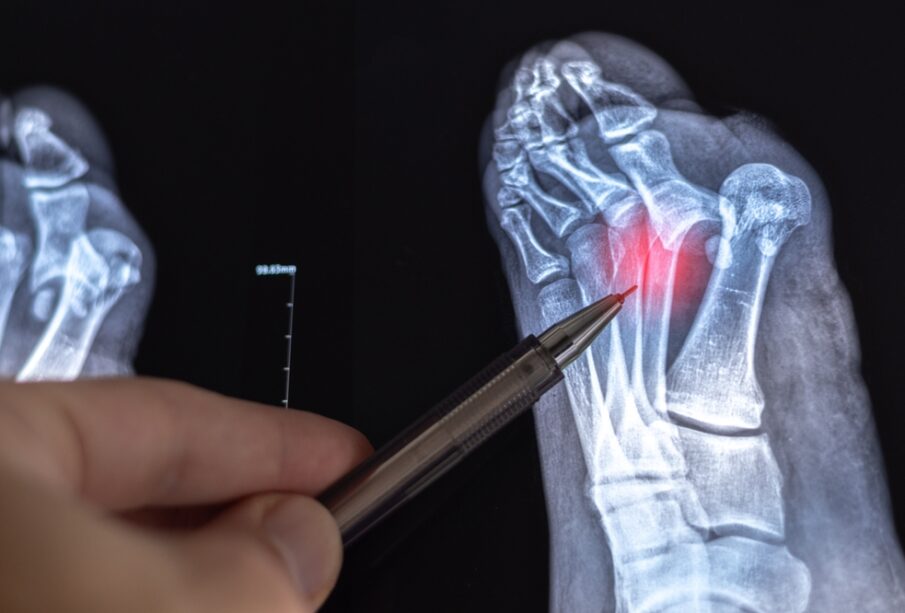

Šiame gydymo būde derinamos dvi pagrindinės dalys. Atvira repozicija – tai momentas, kai chirurgas atveria pažeistą vietą ir rankiniu būdu sugrąžina lūžusius kaulo galus į teisingą padėtį. Kita dalis – vidinė fiksacija, apima specialių medicininių implantų įtvirtinimą kaulo viduje ar išorėje, kad lūžis išliktų stabilus gijimo metu. Tam naudojamos plokštelės, varžtai, smeigtukai ar strypai – priklausomai nuo kaulo ir traumos pobūdžio.

Po to vidiniam fiksavimui įstatomi metaliniai implantai: gali būti įsukamos plokštelės, prisukami varžtai, įvedami metaliniai strypai į kaulo kanalą arba naudojami specialūs laikikliai (pvz., Kirtchner vielos). Tokie laikikliai užtikrina, kad gijimo laikotarpiu kaulas liktų stabilus ir išlaikytų taisyklingą formą.